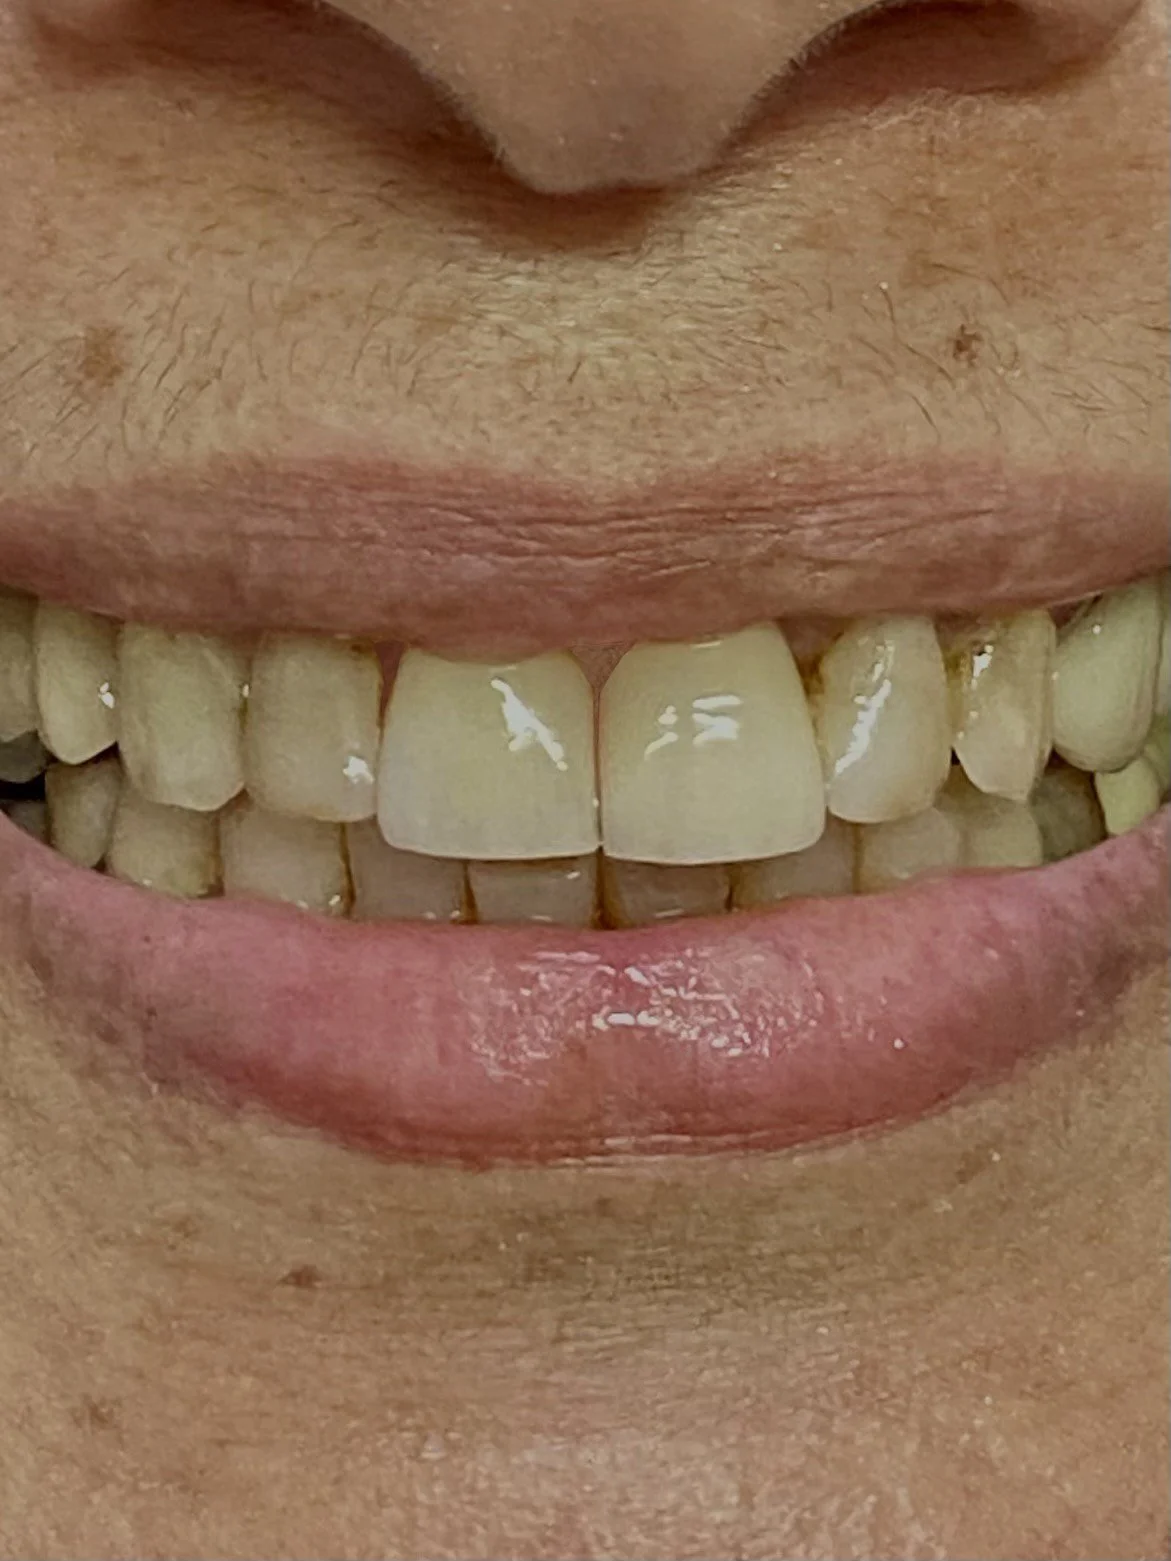

The completed aesthetic and functional occlusal bite case in hinge bite.

The completed facial appearance with significantly improved facial and dental symmetry, without the need for facial surgery.